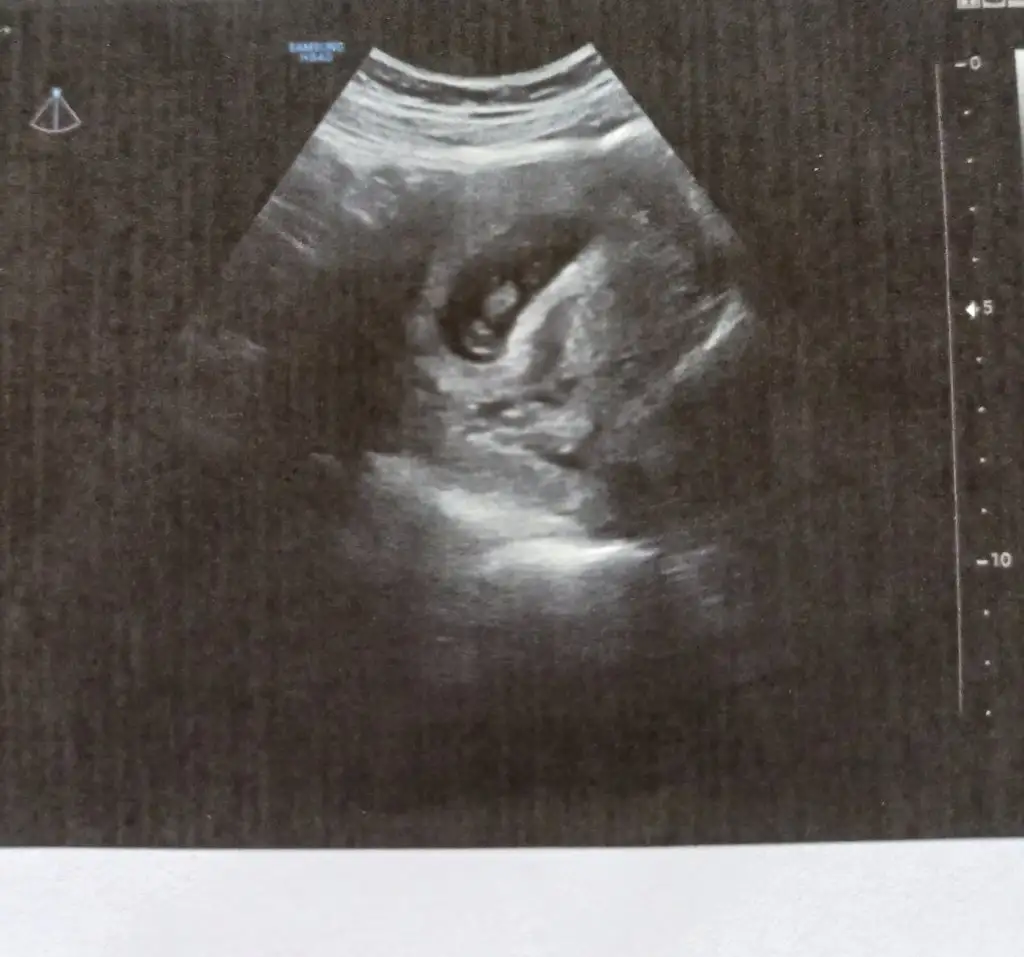

merhaba banada tahminde bulunabilirmisiniz rica etsem.

Karindan ultrasonmerhaba banada tahminde bulunabilirmisiniz rica etsem.

paşa gibi 17 haftalık olmuş söyleme diler mi